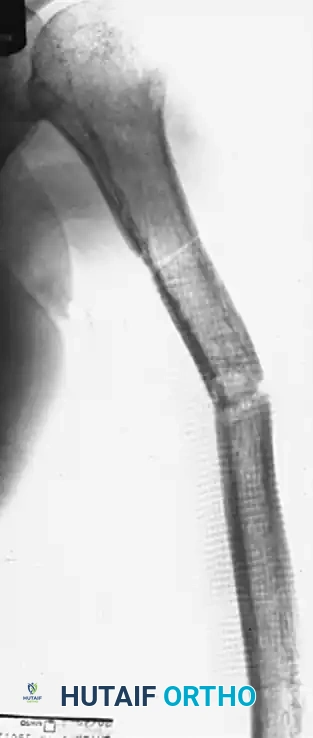

FIGURE 59-30 A: Nonunion of the middle third of the humeral shaft demonstrating significant angulation and regional osteoporosis.

FIGURE 59-31 A: Preoperative radiograph of a recalcitrant humeral diaphyseal nonunion.